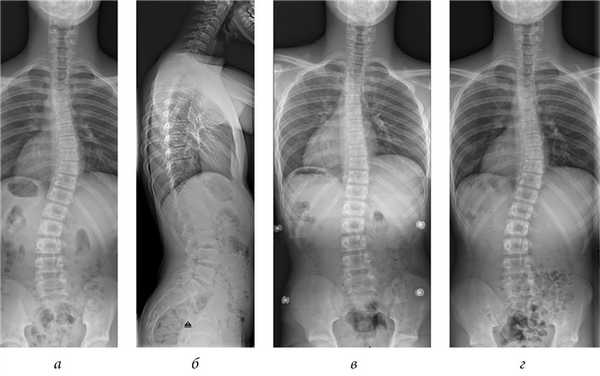

Рис. 1. Мальчик, 12 лет, со сколиозом (а) и нормальной кривизной позвоночника в сагиттальной плоскости (б). Сколиоз можно было эффективно скорректировать с помощью корсета Шено (в). На 6-м месяце наблюдения после окончания ношения корсета деформация позвоночника характеризовалась исходными показателями (г)